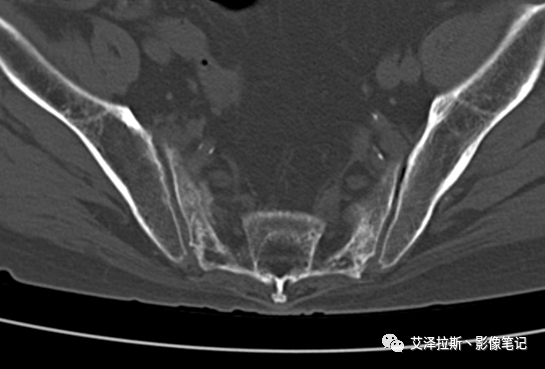

病例1:患者,女性,88岁,重度骨质疏松。

CT平扫:

X线、CT:骶骨重度骨质疏松,双侧骶骨翼皮质断裂,分别见迂曲走行的纵行透亮线位于骶孔外侧,大致与骶髂关节间隙平行,骨折端局部可见骨痂、骨质硬化。

骶骨功能不全骨折

①单侧或者双侧骶骨翼骨折,典型者呈“H”形,即“Honda征”;

②骨折线位于骶孔外侧(如下图,主要发生于1区),通常可能会伴随耻骨的功能不全骨折(如:病例2 右侧耻骨上支骨折,L5双侧横突骨折);

③愈合期骨折线模糊,骨痂形成,骨质硬化;